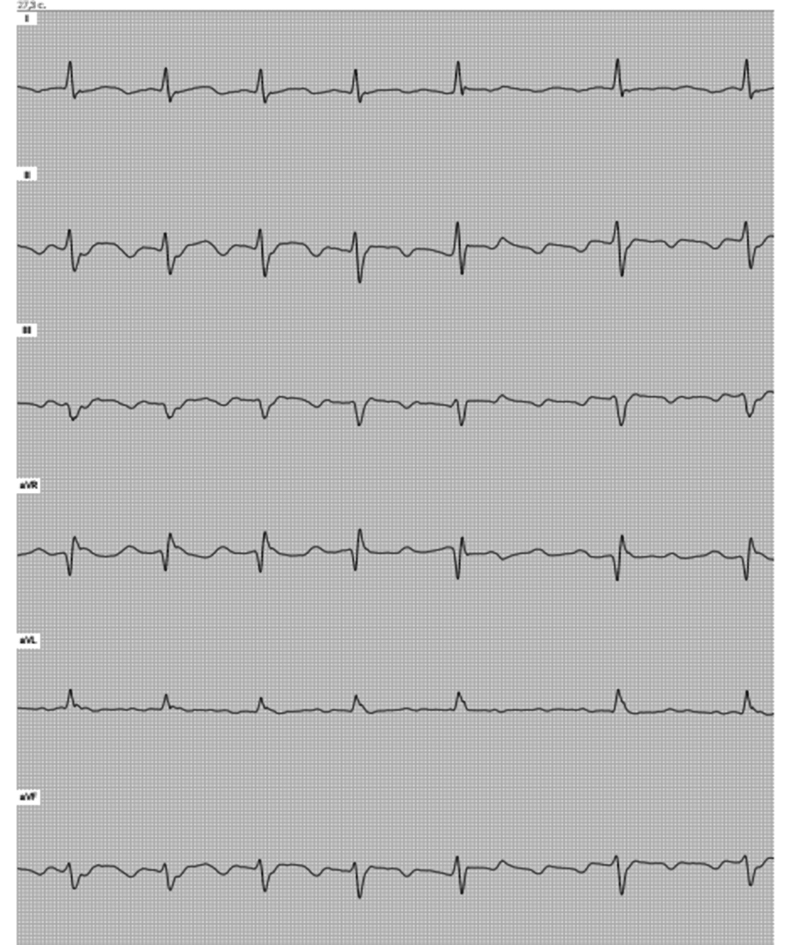

На 1-м этапе сравнивались данные, полученные с помощью мобильного ЭКГ-устройства и с помощью стационарного электрокардиографа в 12 отведениях. Полученные данные совпали в 10 случаях из 10. Сравнивались интервалы P–Q, R–R, Q–T, зубец Р и комплекс QRS. Один из примеров сравниваемых кардиограмм представлен на рис. 3, 4.

Рис. 3. Пациент Б., 20 лет. ЭКГ, записанная стационарным электрокардиографом: Р — 80 мс, P–Q — 160 мс, QRS — 90 мс, Q–Т — 420 мс. Ритм синусовый, нормальное положение электрической оси сердца (ЭОС)

Рис. 4. Пациент Б., 20 лет. ЭКГ, записанная устройством ECG-Dongle: Р — 80 мс, P–Q — 160 мс, QRS — 90 мс, Q–Т — 420 мс. Ритм синусовый, нормальное положение ЭОС